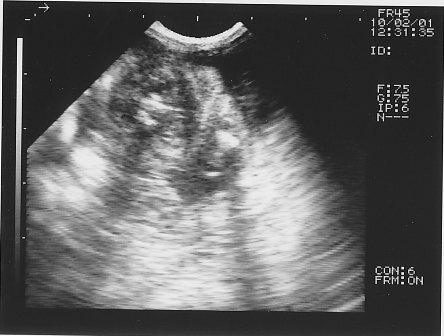

予定日まで1週間ほどになり、エコー検査の時期到来☆

胎児の心臓や肝臓、肋骨に至るまでが写り~の

今回のエコーで、3頭のパピーが確認できました。